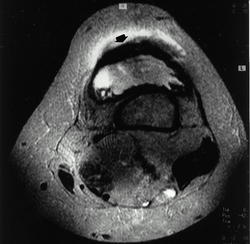

Снимки 4,5,6 пациентки, которой была сделана резекция бедренной кости с эндопротезированием коленного сустава 30 лет назад по поводу остеосаркомы. Расшатывание эндопротеза клинически стало себя проявлять 5 лет назад (снимок 4), далее довольно быстро прогрессировало, что по-видимому усугубилось присоединившимся остеомиелитом (снимки 5, 6 - теперешние). Пришлось выполнить ампутацию, тем не менее, человеку дали 25 лет нормальной, полноценной жизни.